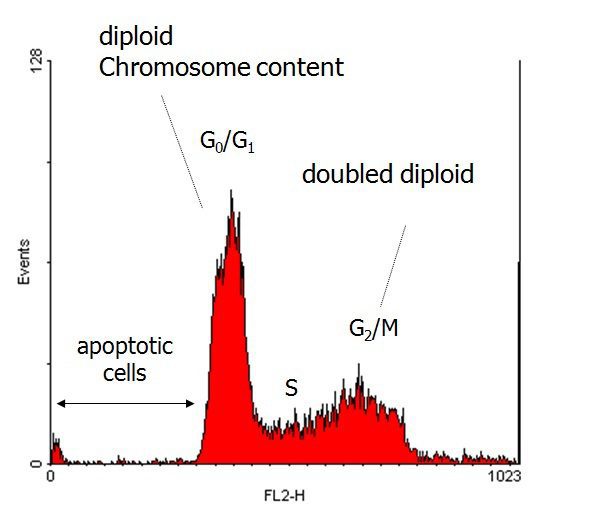

- Evaluation of cell apoptosis by flow cytometry

- Investigation of mitosis cycle in dividing cells